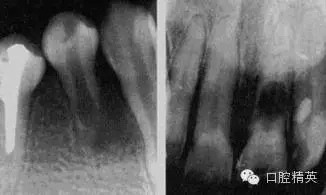

急性化膿性根尖周炎又稱急性牙槽膿腫,是由急性漿液性根尖周炎發(fā)展而來(lái)的,也可由慢性根尖周炎急性發(fā)作所致。急性化膿性根尖周炎在其發(fā)展過(guò)程中,因其膿液所在部位不同而劃分為根尖膿腫、骨膜下膿腫和黏膜下膿腫三個(gè)階段,主要癥狀為疼痛和腫脹,嚴(yán)重者伴有全身癥狀。

1.根尖膿腫 患牙有自發(fā)性、持續(xù)性、定位性劇烈跳痛,患牙浮起,咬合痛;檢查患牙叩痛、松動(dòng)明顯,根尖部牙齦潮紅,有輕度捫痛。牙髓無(wú)活力。

2.骨膜下膿腫 患牙持續(xù)性劇烈跳痛達(dá)最高峰,更覺高起、松動(dòng),觸痛劇烈,相應(yīng)頜面部軟組織腫脹、壓痛,并伴有全身癥狀;檢查患牙為重度叩痛、Ⅲ°松動(dòng),牙齦紅腫,移行溝變平,壓痛明顯,捫診有深部波動(dòng)感,牙髓無(wú)活力。

3.黏膜下膿腫 膿液已達(dá)黏膜下,疼痛減輕,全身癥狀緩解;檢查患牙叩痛(+)—(++),松動(dòng)I°,根尖區(qū)黏膜腫脹呈半球形隆起,波動(dòng)感明顯,牙髓無(wú)活力。